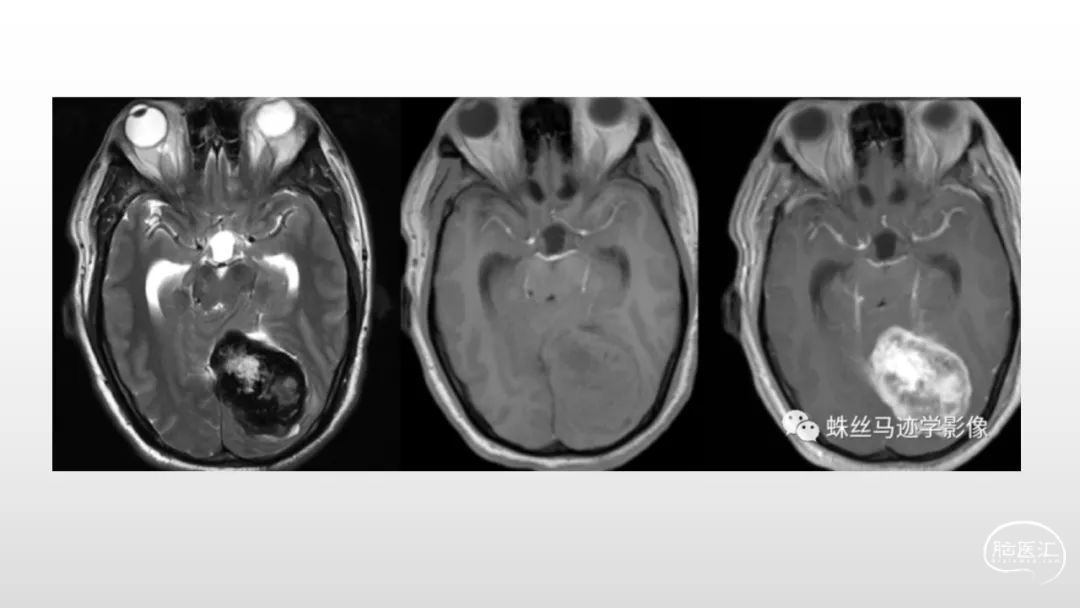

颅脑影像诊断基础知识讲座:脑膜病变